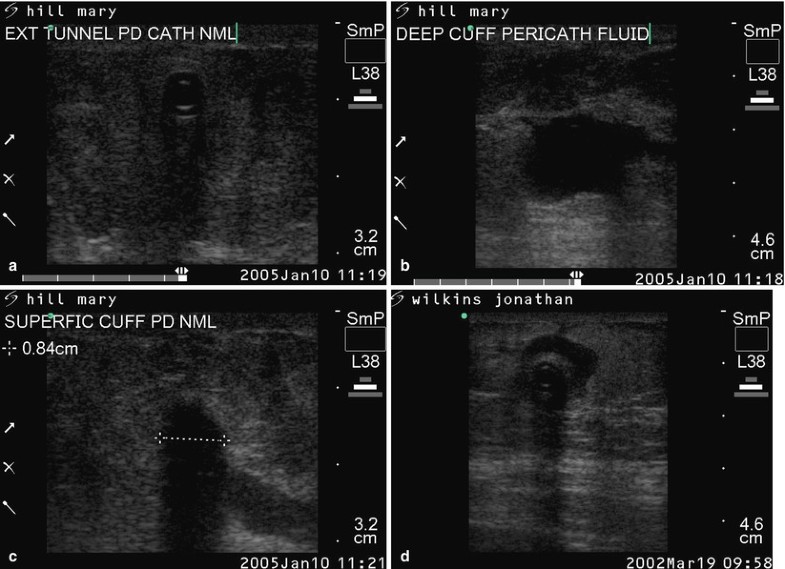

Bedside Ultrasonography of the Peritoneal Dialysis Catheter Renal Dialysis Catheter Ultrasound For sonographic assessment of the pd catheter, a linear (= high frequency) transducer is preferred as it provides adequate visualization of the superficial structures including the catheter. Many studies confirmed the pivotal role of ultrasound in this. Most guidelines recommend using doppler ultrasound (du) to surveil the avf for hd, but its use must not only be limited to surveillance. Dialysis Catheter Ultrasound.

Figure 20 from Imaging and Peritoneal Dialysis Catheters. Semantic Dialysis Catheter Ultrasound For sonographic assessment of the pd catheter, a linear (= high frequency) transducer is preferred as it provides adequate visualization of the superficial structures including the catheter. Most guidelines recommend using doppler ultrasound (du) to surveil the avf for hd, but its use must not only be limited to surveillance as it can also be used for needling. Many studies. Dialysis Catheter Ultrasound.